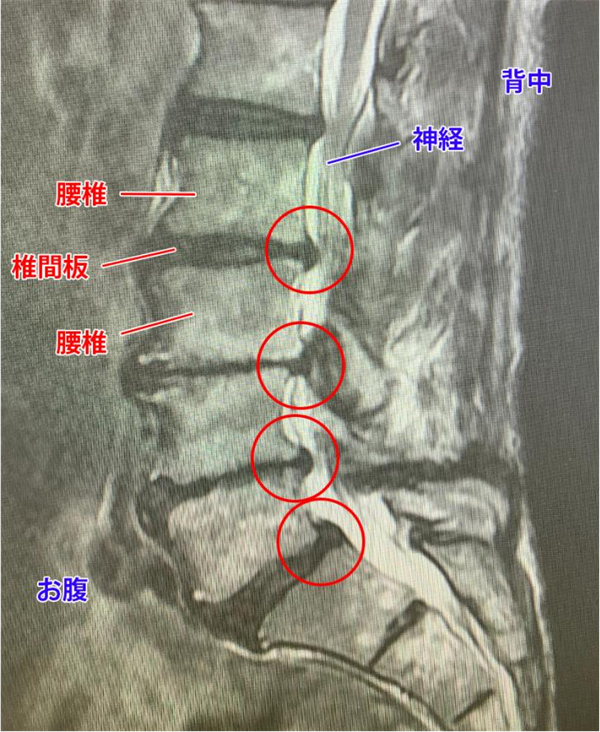

在印度尼西亚,有一位对体育运动充满无限热爱的女性,却因腰痛与坐骨神经痛的纠缠,不得不暂时放下跑鞋和球拍,远离了她热爱的运动场。面对日益加剧的腰痛和神经疼痛,她并未放弃希望。在了解到野中腰椎医院有DST疗法后,她决定跨越距离,通过远程诊断预约就诊,勇敢地踏上了康复之路。在医院里,她感受到了家一般的温暖。专业翻译全程陪同,详细解释每一项检查的意义,让她在异国他乡也能安心接受治疗。腰椎核磁共振的结果虽然令人担忧,但经过医生们的精心规划与治疗,DST疗法成功修复了她受损的椎间盘,减轻了炎症,缓解了神经压迫。随着治疗的深入,她逐渐感受到了身体的变化:腰痛减轻了,坐骨神经痛也消失了。如今,这位热爱体育运动的女士已经再次穿上跑鞋,拿起球拍,回到了她热爱的运动场上。